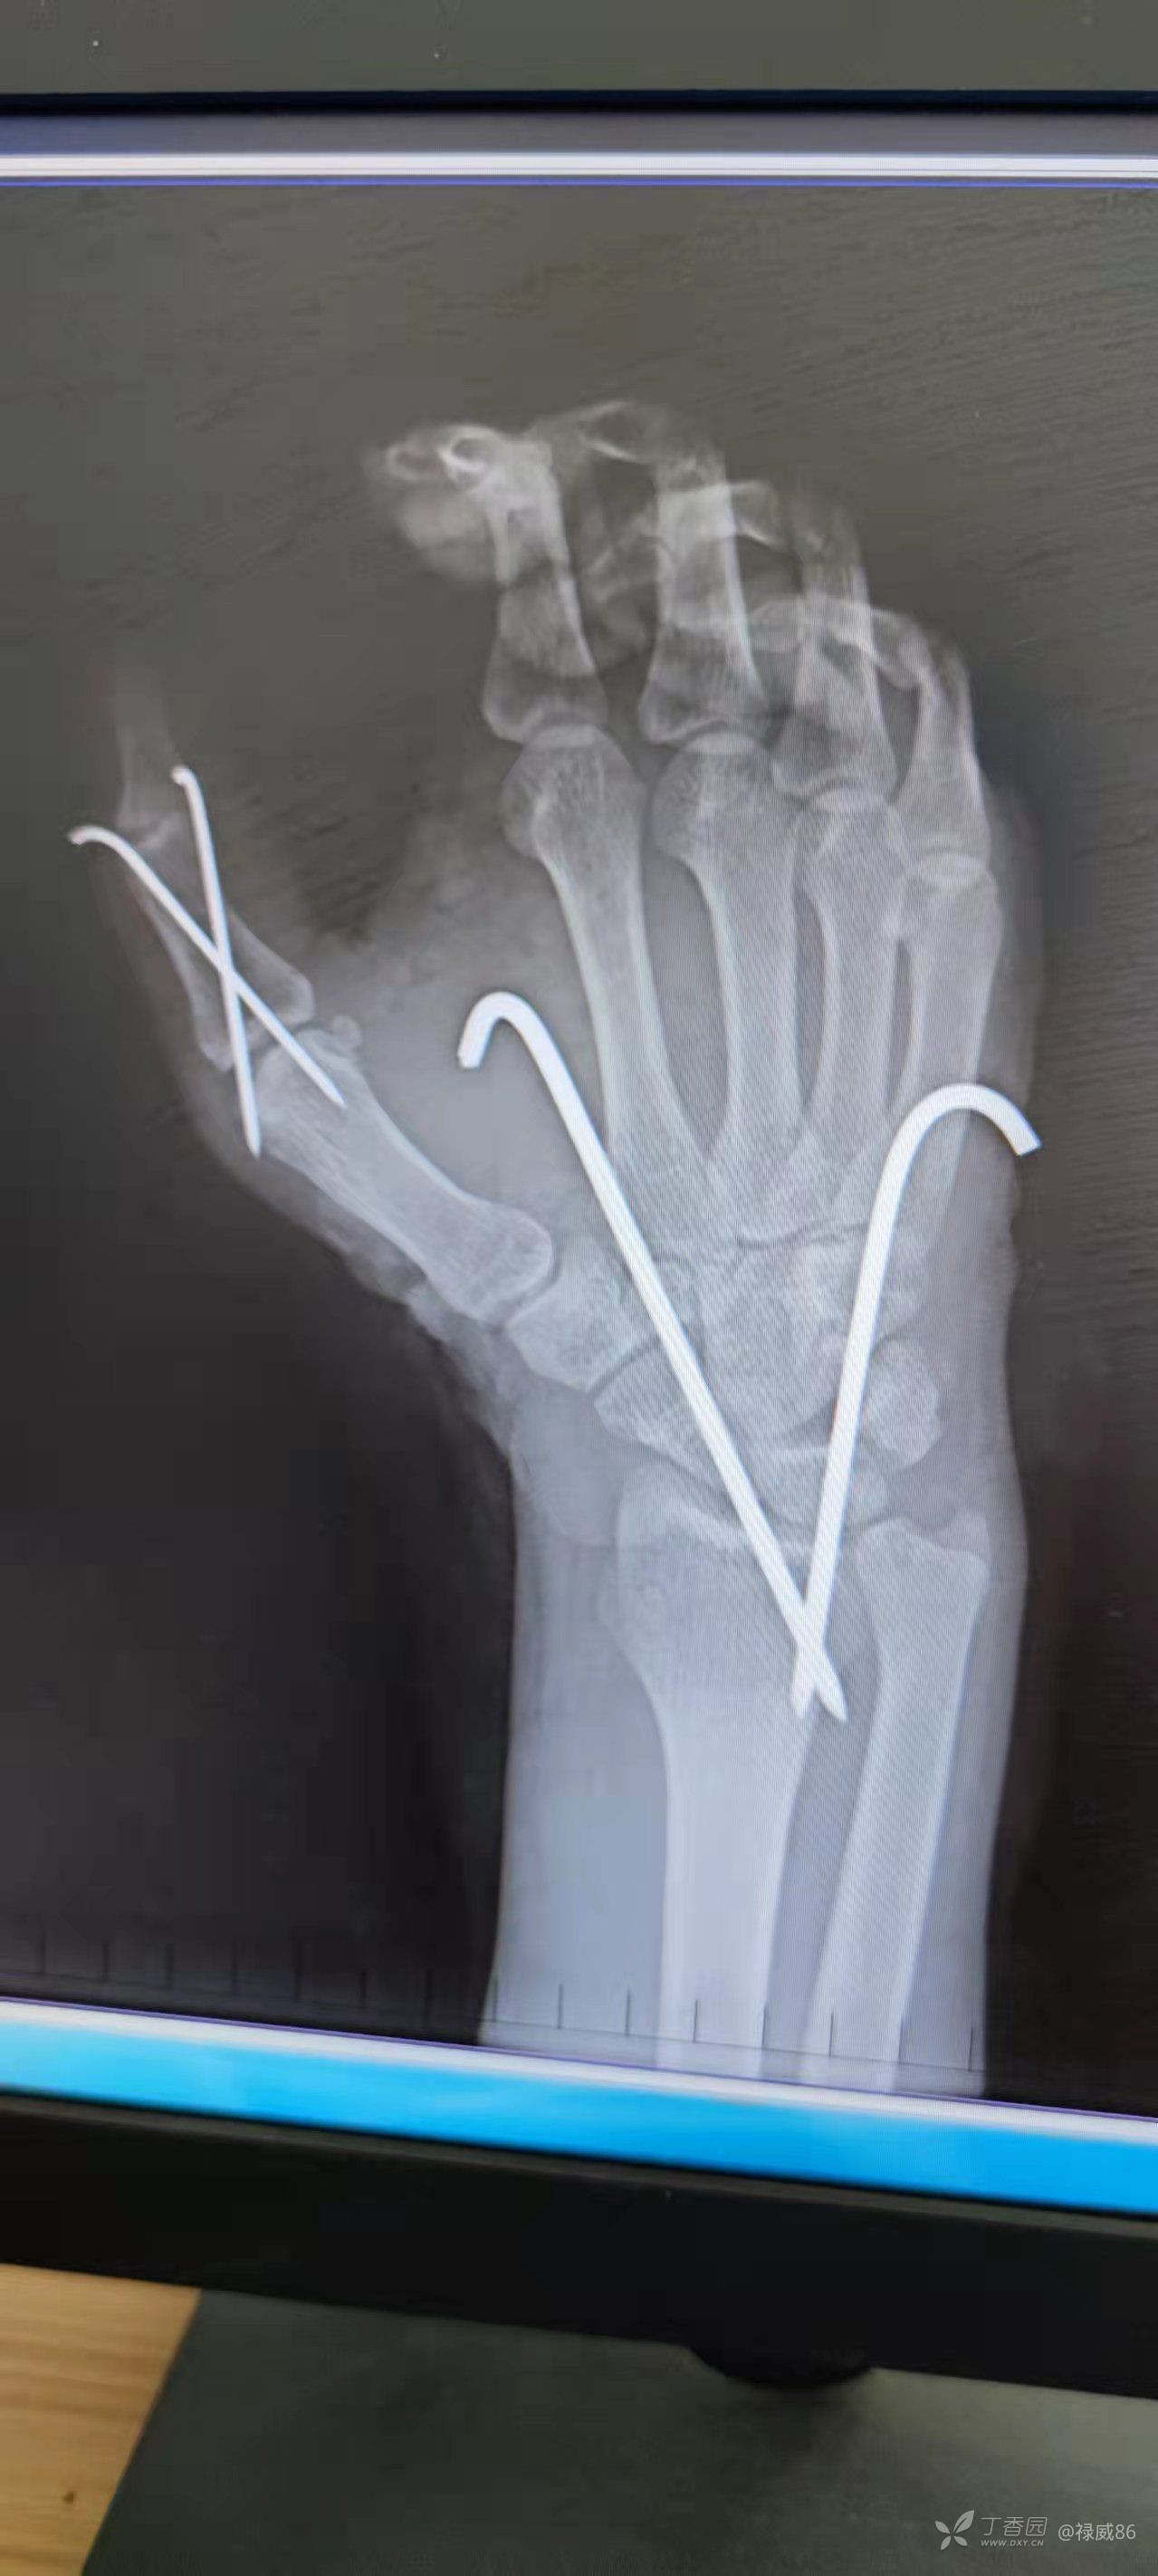

急诊行伤口彻底清创,拇指掌指关节、腕关节脱位复位,肌腱、血管、神经缝合,功能位克氏针固定,一期经皮缝合伤口!使用生理盐水清洗,银离子抗菌液体敷料换药,伤口无感染。

复查X线较拇指掌指关节,腕关节对合关系良好!